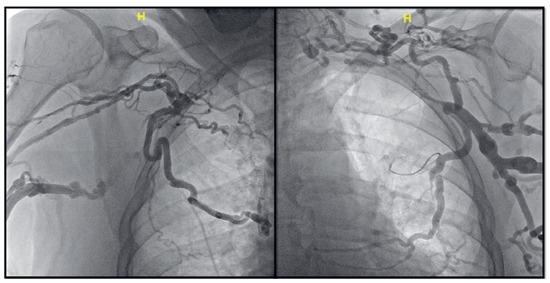

Leadless Pacemaker Placement to Overcome Bilateral Subclavian Vein Occlusion

by Patrick Badertscher, Philip Haaf, Christian Sticherling and Stefan Osswald

Cardiovasc. Med. 2022, 25(3), 92; https://doi.org/10.4414/cvm.2022.02198 (registering DOI) - 1 May 2022

We present the case of a 76-year-old man referred for dual chamber pacemaker implantation for high-grade atrioventricular block. Prior to dual-chamber pacemaker implantation, the following contrast venograms are obtained. How do you proceed [...] Full article